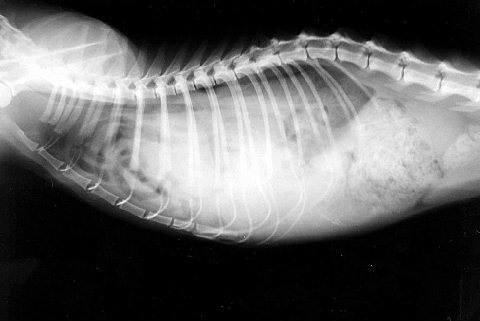

次のレントゲン写真は「横隔膜へルニア」です。

横隔膜は胸部と腹部の境界となる筋肉で、呼吸をする際に重要な役割を持っています。

胸腔内は「陰圧」(真空状態)となっており、横隔膜が破れると腹腔内の臓器が一気に胸腔内に入り込みます。

その結果、心臓・肺が圧迫され呼吸困難となります。

原因は交通事故が圧倒的に多いですね。

写真向かって左側が頭なんですが、胸腔内の頭側に小腸のガス像が見えます。

この場合はお腹の臓器はお腹に戻してから破れた横隔膜を元の位置で縫合します。

その後胸腔内に溜まっている空気を抜いておかねばなりません。